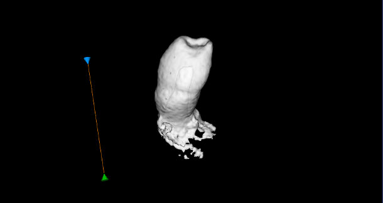

Opisao je i najšire prihvaćenu teoriju preosetljivosti – hidrodinamičku teoriju. Objašnjavajući hidrodinamički mehanizam zuba, pozvao se na istraživanje koje se bavilo proučavanjem osetljivog i neosetljivog zuba. Rezultati istraživanja su pokazali da unutar osetljivog zuba ima i do osam puta više dentinskih tubula, te da je njihov prečnik dva puta širi u odnosu na tubule neosetljivog zuba.